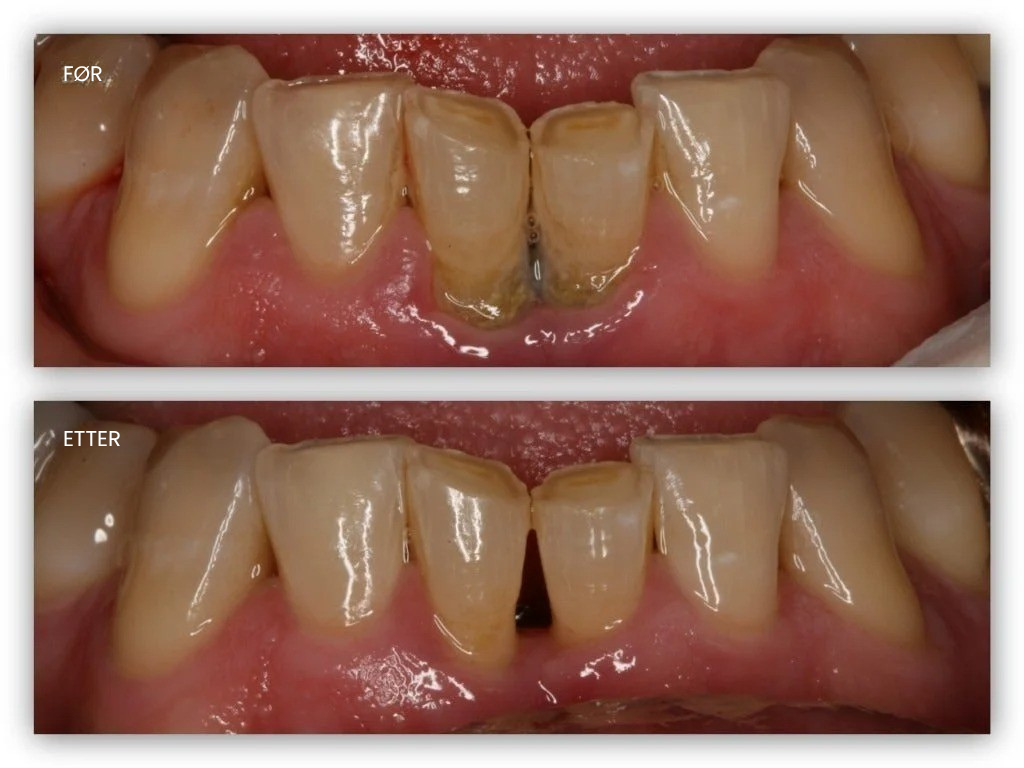

Når tannkjøttet trekker seg tilbake og blottlegger de sensitive tannrøttene, blir selv vanlige aktiviteter uutholdelige på grunn av det konstante ubehaget.

Ser tennene dine lengre ut enn før fordi tannkjøttet trekker seg tilbake?

Teeth Repair Gel danner et tynt beskyttende lag over tilbaketrukket tannkjøtt og eksponerte røtter. De aktive partiklene trenger dypt inn i tannkjøttvevet, nærer cellene og gir de essensielle "byggesteinene" som trengs for sunn vekst akkurat der tilbakegangen har oppstått.

De aktive ingrediensene erstatter skadede celler med lignende byggesteiner og utløser regenerasjon av nytt, friskt vev som dekker de smertefulle eksponerte røttene.